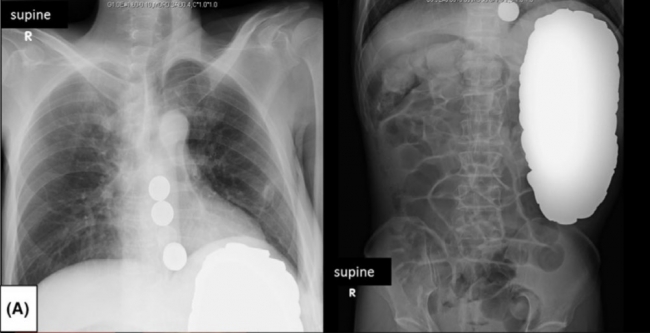

Alınan radyasyon görüntülerinde hastanın midesinde daire şeklinde cisimler tespit edildi. Hastayı hemen ameliyata alan doktorlar, hastanın midesinden bin 894 adet bozuk para çıkardı.

Hastanın midesinden 100'den fazla 1 yen, 99 adet 5 yen, bin 642 adet 10 yen, 8 adet 50 yen ve 5 adet 100 yen çıkartıldı.